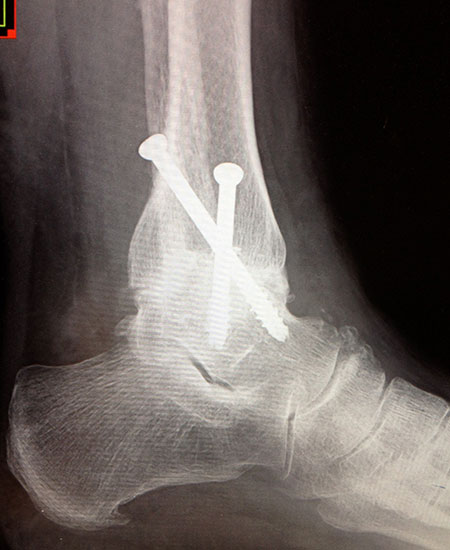

Fixation mit mindestens 2, ggf. 3 kanülierten Schrauben (6,0, 6,5 oder 7,0 mm), die von medial-kranial und lateral-kranial nach kaudal oder von anterior-kranial nach posterior-distal (Abb. 6) in den Talus unter BV-Kontrolle in 2 Ebenen eingebracht werden (Sabo 2014). Im amerikanischen Sprachraum ist die Verwendung der von dorsal-lateral paraachillär nach anterior-medial in den Corpus tali gerichteten Zugschraube geläufig („home run-screw“) (Abb. 7). Es ist darauf zu achten, das untere Sprunggelenk nicht mit Schrauben zu perforieren. Idealerweise spannen die Kompressionsschrauben, deren Gewindegänge nur im Talus liegen sollten diesen stabil in die Malleolengabel ein.

Abbildung 6

Abbildung 7